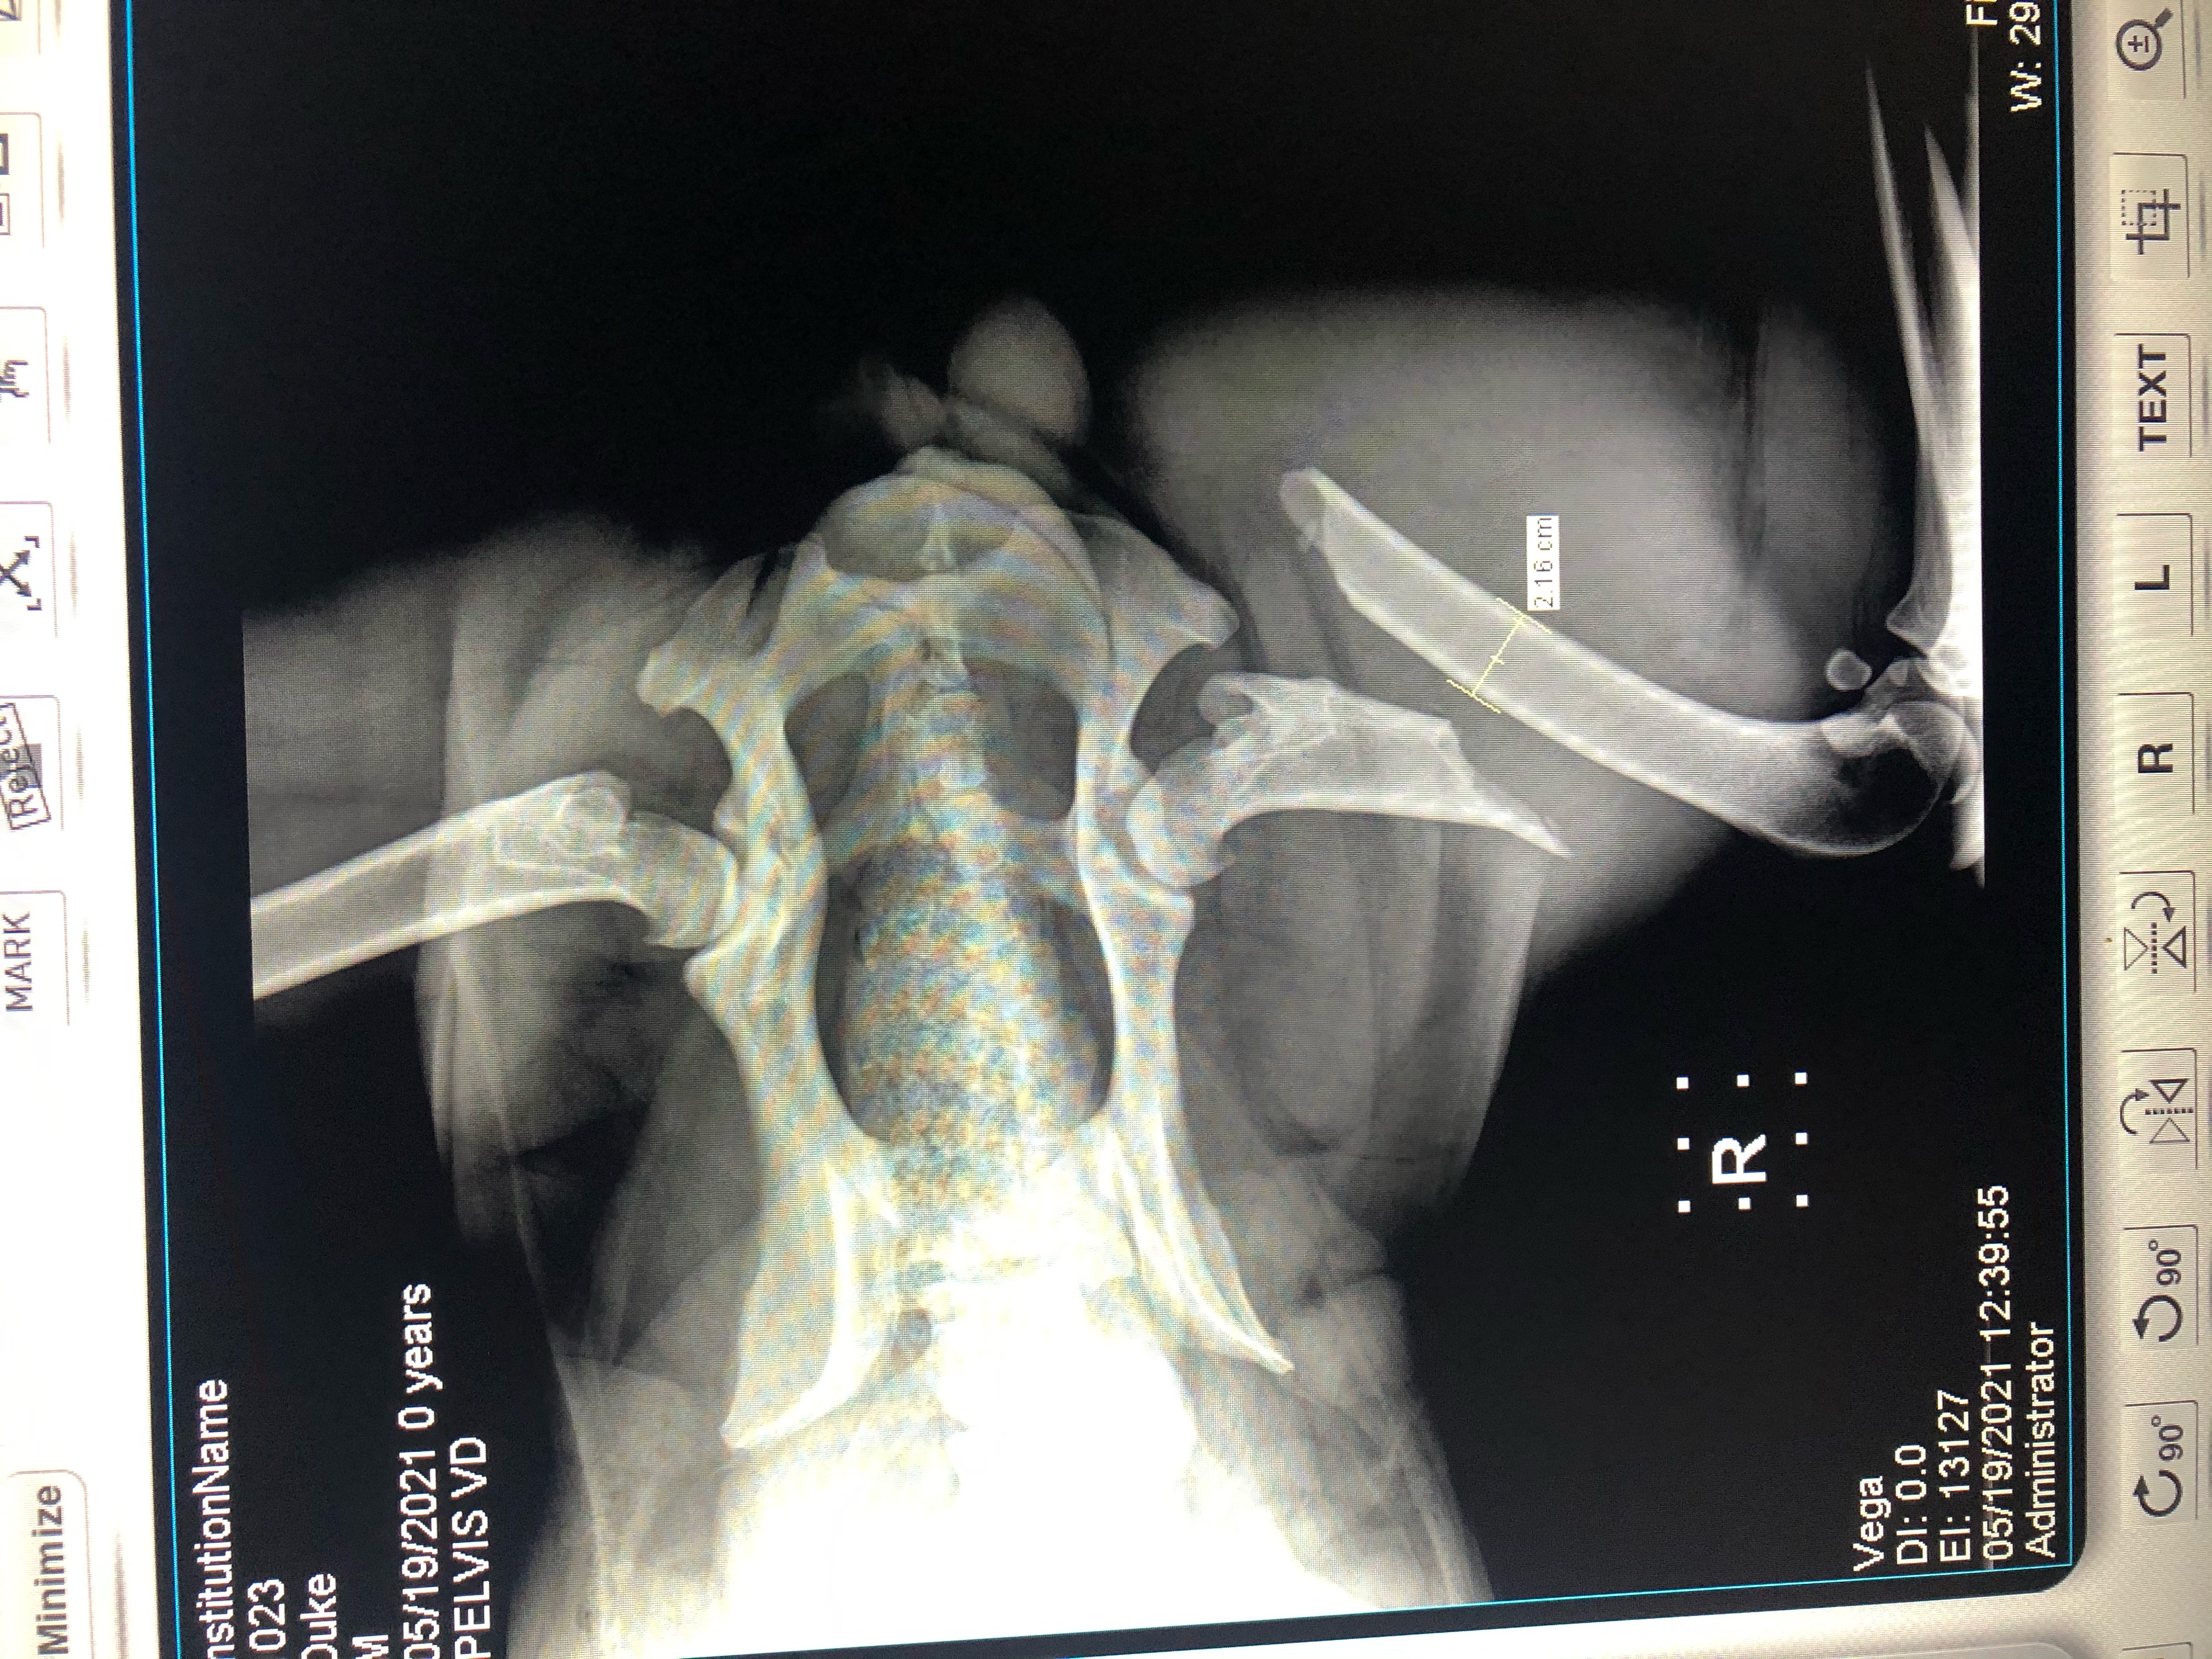

Duke

See the X-ray showing Duke's broken leg here.  The file is 3 MB.